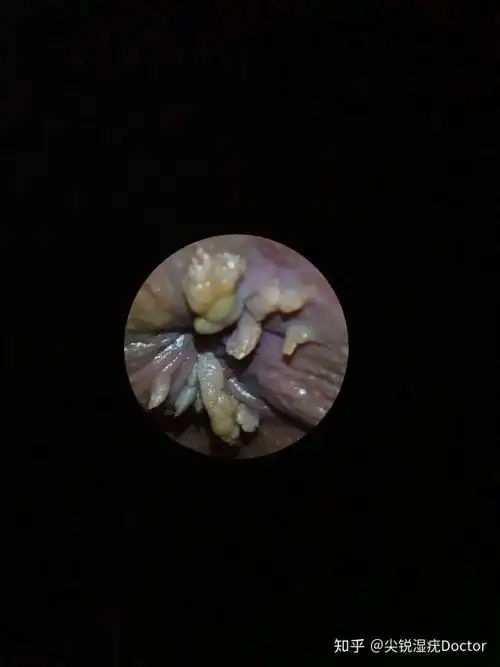

巨大的尖锐湿疣怎么治疗

尖锐湿疣,肛周疣体症状图片

尖锐湿疣的症状图片